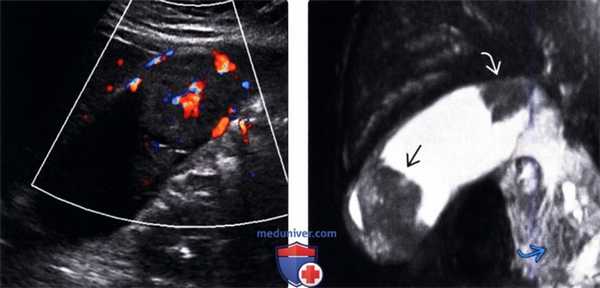

• Цветовая допплерография:

о Зоны васкуляризации в толще объемного образования

о Наличие у полипа крупнее 1 см васкуляризованной сердцевины

(Левый) У пациентки 67 лет с острым панкреатитом на сагиттальном УЗ срезе определяется крупное полипоидное объемное образование дна желчного пузыря, имеющее собственную сосудистую сеть.

(Правый) При МРТ в просвете желчного пузыря визуализируется дольчатое полипоидное образование, гетерогенное и гиперинтенсивное по сравнению с прилегающей печенью. Обратите внимание на угловатый конкремент в шейке желчного пузыря и отечность поджелудочной железы, вызванную острым интерстициальным отечным панкреатитом.